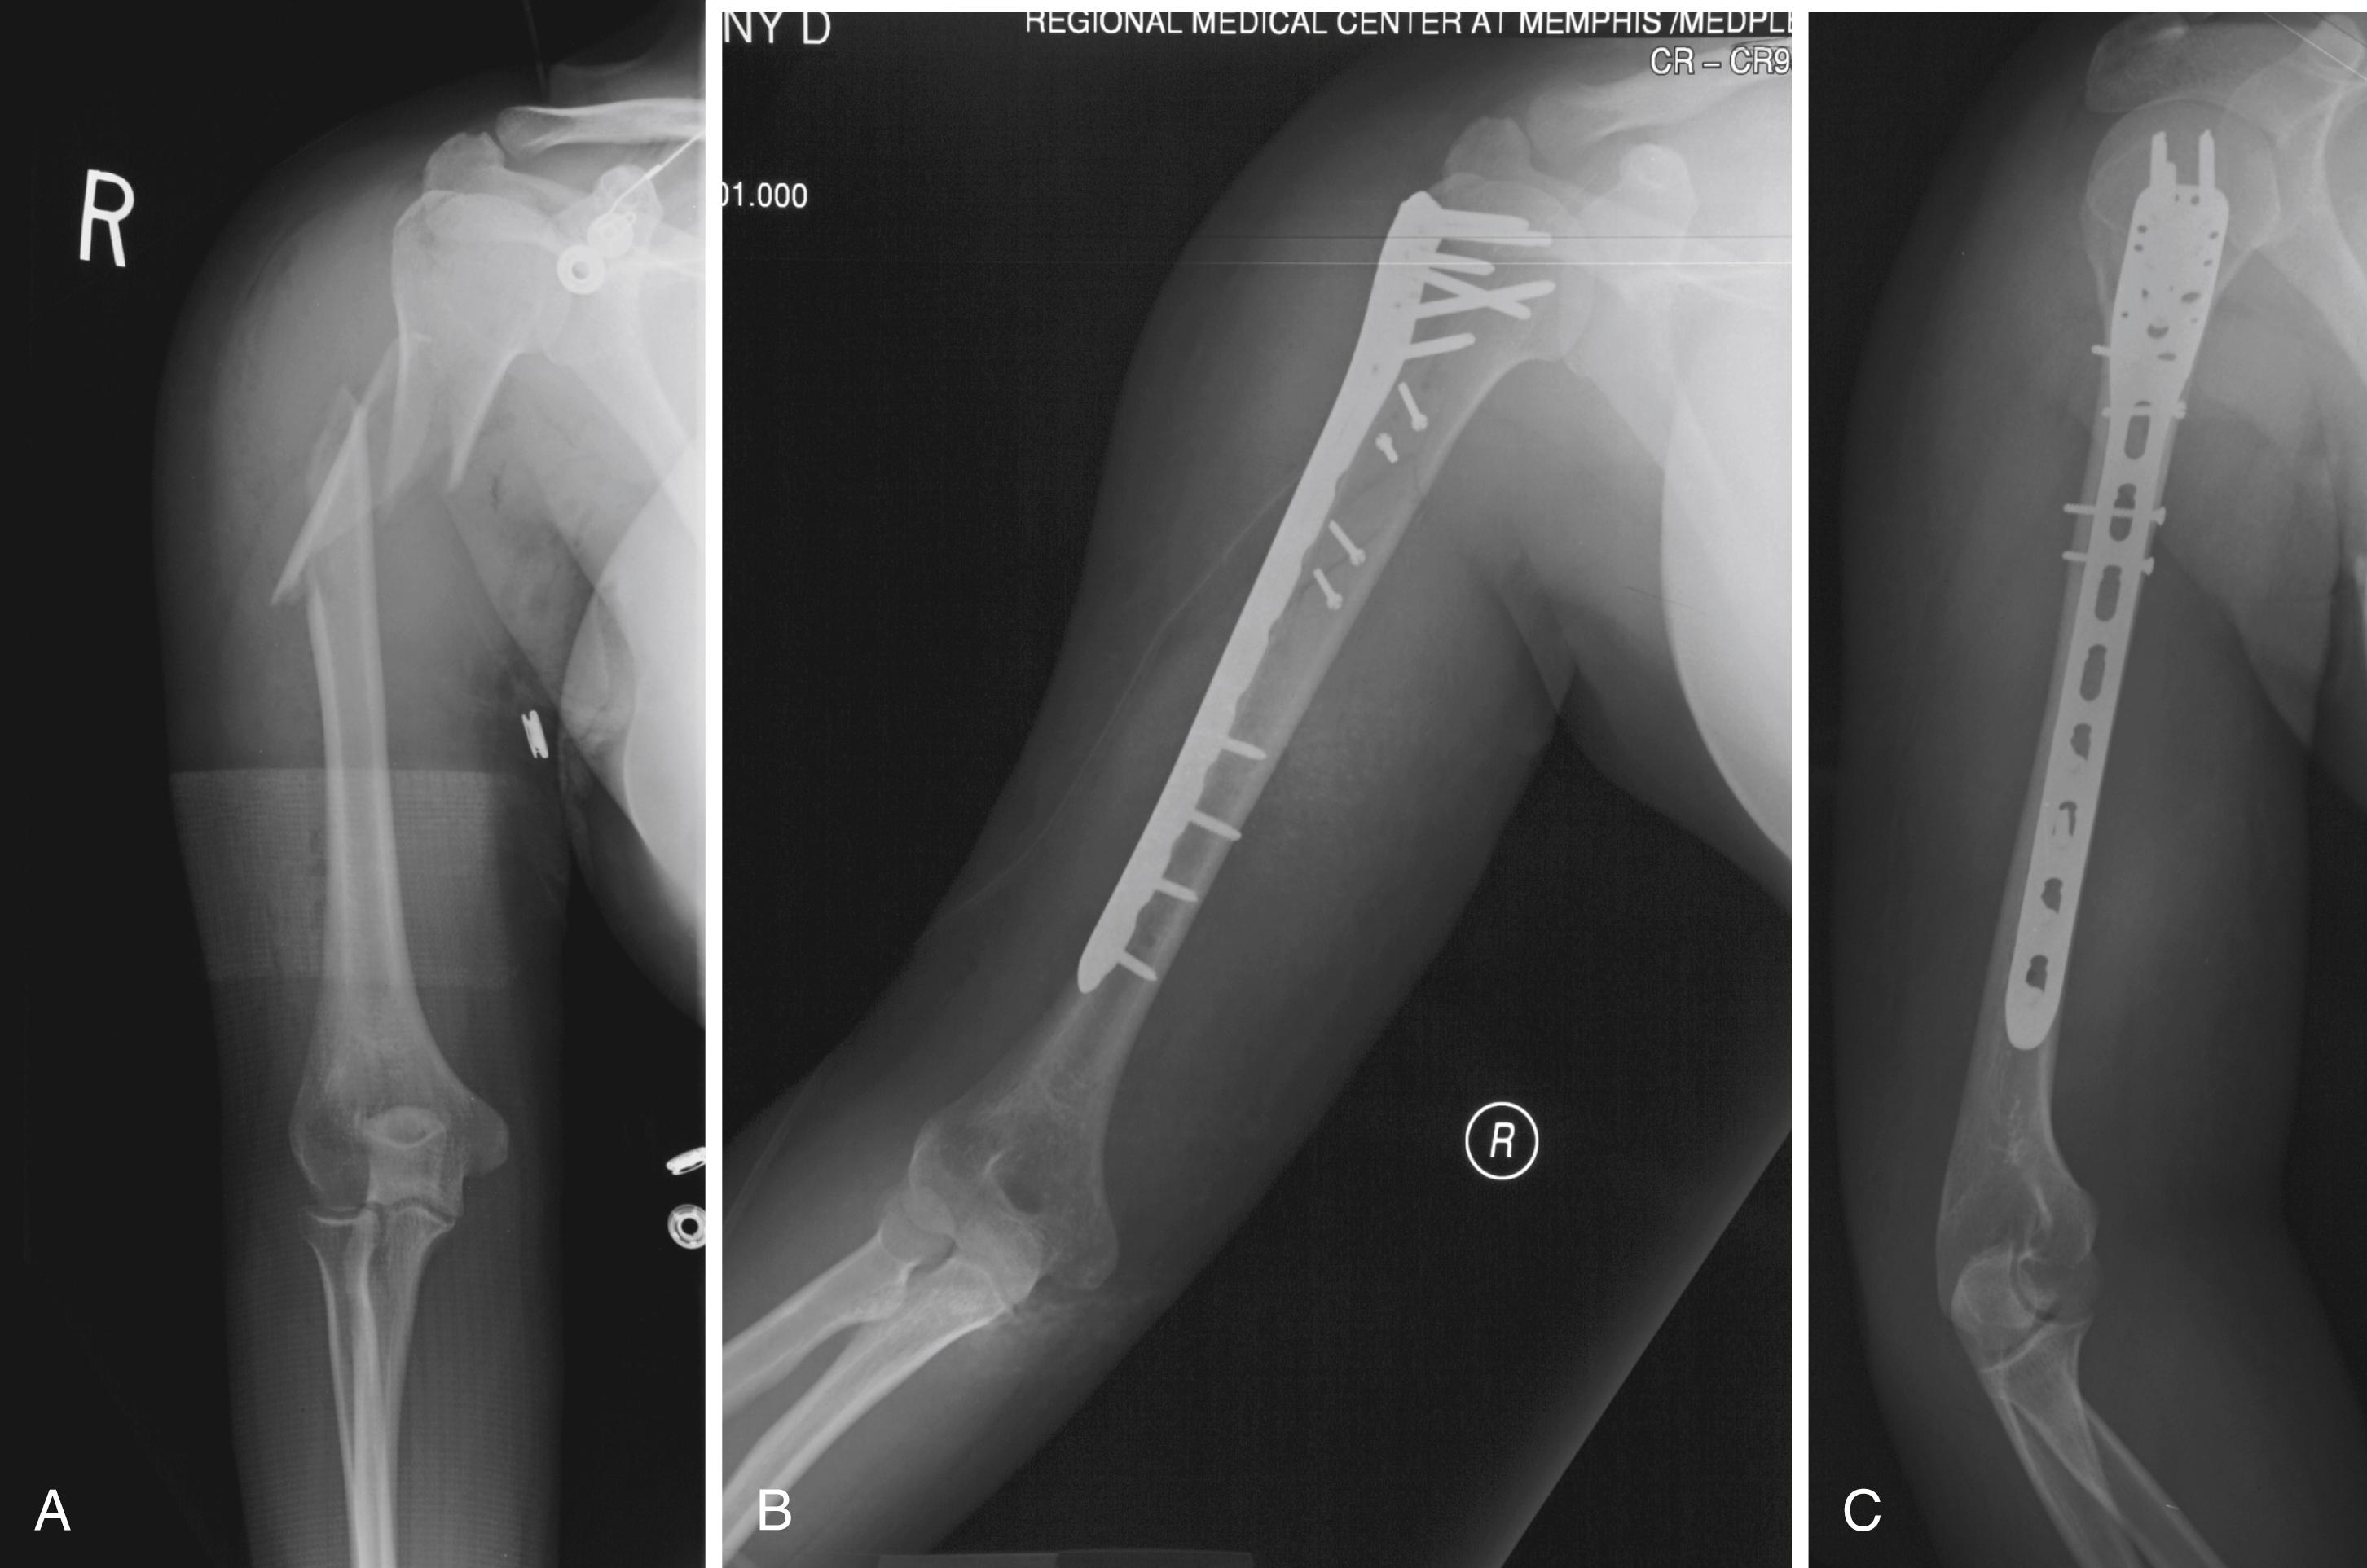

Fractures of the Humeral Shaft

Fractures of the humeral shaft account for approximately 3% of all fractures; most can be treated nonoperatively. Charnley stated, “It is perhaps the easiest of the major long bones to treat by conservative methods.” The range of motion afforded by the shoulder and elbow joints, coupled with a tolerance for small amounts of shortening, allow radiographic imperfections that cause minimal functional deficit and are well tolerated by the patient. Historically, methods of conservative treatment have included skeletal traction, abduction casting and splinting, Velpeau dressing, and hanging arm cast, each with its own advantages and disadvantages.

Functional bracing has essentially replaced all other conservative methods and has become the “gold standard” for nonoperative treatment because of its ease of application, adjustability, allowance of shoulder and elbow motion, relatively low cost, and reproducible results. Initially popularized by Sarmiento in 1977, the functional brace works on the principles of the hydraulic effect of the brace, active contraction of the muscles, and beneficial effect of gravity. Union rates of 77% to 100% have been reported with this technique (Papasoulis et al. 2010). In a randomized controlled trial comparing minimally invasive plate osteosynthesis and functional bracing, Matsunaga et al. reported a 15% nonunion rate with functional bracing. Driesman et al. reported 84 consecutive patients with diaphyseal humeral fractures managed nonoperatively. Within 6 months 87% of fractures healed. They noted that a mobile humeral shaft fracture at the 6-week follow-up visit was a predictor of nonunion with 82% sensitivity and 99% specificity. This author counsels patients appropriately as to risk of developing a nonunion if fracture site variability exists at 6 weeks. We currently use a coaptation splint or hanging arm cast for the first 7 to 10 days to allow pain to subside and then convert to a prefabricated functional brace. The use of a sling is discouraged to avoid varus and internal rotation deformities. Pendulum exercises are started early, and use of the extremity is encouraged as tolerated, avoiding active shoulder abduction. The brace is worn until the patient is pain free and there is radiographic evidence of union. Skin maceration is a concern, so daily hygiene is stressed. Morbid obesity may increase the risk of varus deformities; however, these deformities are more of a cosmetic issue than a functional issue and often are not evident in an obese arm. Shields et al. showed no correlation between residual deformity and functional outcome scores.

A nonrandomized study by Jawa et al. compared outcomes in 21 distal-third diaphyseal fractures treated with functional bracing to those of 19 treated with plate-and-screw fixation. Operative treatment resulted in more predictable alignment and faster healing but was associated with more complications, such as iatrogenic nerve injury, loss of fixation, and infection. Plate-and-screw fixation was done in two patients initially treated with bracing because of concerns about alignment. Complications associated with bracing included skin breakdown and malunion. The advantages, disadvantages, and risks of both nonoperative and operative treatment should be discussed with the patient before a decision is made.

Indications for operative treatment

The choice of operative treatment for a humeral shaft fracture depends on multiple factors. McKee divided the indications for operative treatment into three categories: (1) fracture indications, (2) associated injuries, and (3) patient indications ( Box 57.2 ). Some indications are more absolute than others. Failure of conservative treatment, pathologic fracture, displaced intraarticular extension, vascular injury, and brachial plexus injury almost always require surgery. Other conditions, such as minimally displaced segmental fractures and obesity, are only relative indications. Our most common indication for operative treatment is early mobilization of patients with polytrauma. Treatment decisions must take all factors into consideration, tailoring the treatment to the specific patient.